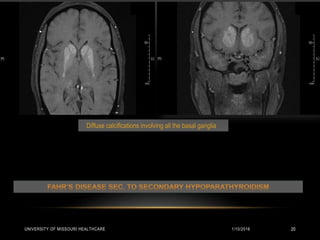

RADIOLOGY

CT Head:

• Scattered hyperdense foci visualized in bilateral basal ganglia and subcortical white

matter of the bilateral occipital lobes and within cerebellum. Right rectus muscle is slightly

more prominent. Findings consistent with Fahr’s disease.

MRI of the Brain:

• Bilateral symmetrical calcification in bilateral basal ganglia, thalami, cerebellar dentate

nuclei suggestive of Fahr’s disease.

• Right sided proptosis with enlargement and increased enhancement of the inferior rectus

and medial rectus. Increased enhancement of the left superior oblique muscle. Primary

consideration is Thyroid orbitopathy / Pseudotumor / Myositis.

Diffuse calcifications involving all the basal ganglia